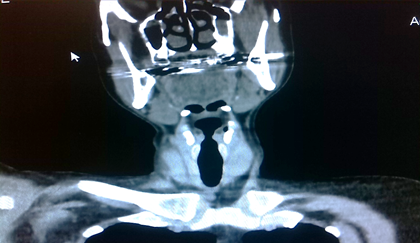

Pruebas de laboratorio: se aprecia leucocitosis en 12.000cel/mm3 y luego progresa a 24.500cel/mm3, polimorfo nuclear 90%, valores de glucosa en sangre elevada. Se le realiza rayos x de cuello (Figura 2. Anexos), y ecosonograma de región cervical, donde se describe una lesión ocupante de espacio alrededor de la tráquea hacia el lado izquierdo, de 4x 2 cm, heterogénea de bordes bien circunscritos. No presenta vascularidad al uso del Doppler. El lóbulo izquierdo del tiroides, muestra efecto de masa en su cara inferior. Concluye con una lesión ocupante de espacio en región traqueal izquierda sugerente de absceso frio. Se le realiza estudio de tomografía computarizada de cuello (Figura. 3, 4, 5. Anexos), y tórax, apreciando en región lateral izquierda del cuello, hiperdensidad paralela a la tráquea y glándula tiroidea, haciendo efecto de masa compresiva sobre las estructuras cercanas.

Figura 4. Tomografía axial computarizada de región cervical. apreciando en región lateral izquierda del cuello, hiperdensidad paralela a la tráquea y glándula tiroidea, haciendo efecto de masa compresiva sobre las estructuras cercanas.

Fuente: Fotografía realizada por Dra. María Pulgar.